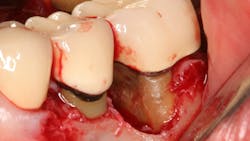

- Fractured calculus. Calculus can chemically bond to the hydroxyapatite crystalline structure of cementum, and that union can be stronger than the cohesive strength within calculus itself.9 When attempting to remove, the calculus can fracture and a basal layer remains firmly attached to the root. Repeated strokes with a scaling instrument result in a “burnished,” or smooth, surface that is often undetectable by a periodontal probe.

A patient had four quadrants of scaling and root planing in the office of her general dentist. Subsequently, three maxillary anterior implants were placed. The patient was scheduled every six months for periodontal maintenance visits. Radiographs taken prior to the scaling and root planing (figure 4) revealed moderate periodontitis with slight vertical bone loss involving the mandibular left first molar. A deep vertical osseous defect on the distal of the second molar was present.